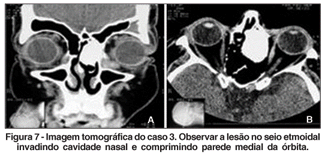

O exame ocular era normal. À ectoscopia havia nódulo móvel, indolor, consistência fibroelástica, no canto nasal do OE. Expressão sobre o saco lacrimal provocava a saída de secreção esbranquiçada. A dacriocistografia mostrou lesão no canto interno do OE, dilatação e obstrução baixa da via lacrimal (Figura 6). Portanto, havia uma dilatação do saco lacrimal, provavelmente secundária à lesão que foi evidenciada na tomografia, sendo também observada a lesão de densidade óssea, localizada no seio etmoidal e invadindo cavidade nasal, compatível com osteoma do etmóide (Figura 7A e B).